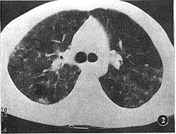

图2 亚急性期,双上肺中外带层磨玻璃样变,小叶间隔增厚结节影

急性期2例(发病2周以内),HRCT表现为双肺模 糊的细小结节影及气腔实变影(图1),同期X线平片呈斑片状浅淡阴影,分布两肺中下肺叶野 。亚 急性期(2~4周),10例,HRCT表现为边缘模糊的小结节影及对称分布的磨玻璃影,边缘趋于 清晰,其中1例合并局限性肺气肿。同期X线平片表现为肺纹理增强,边缘模糊,肺野透亮度 减低。慢性期4例(发病4周以上),其HRCT表现为在小结节、磨玻璃影的基础上出现小叶间 隔增厚,不规则条状影(图3),其中2例出现支气管血管束扭曲,肺结构破坏,并在两肺外带 出现 蜂窝状改变,1例出现间质性肺气肿。同期X线平片在两肺网节状、索条状及蜂窝状改变。所 有病例均未见肺门淋巴结肿大及胸膜改变。

外源性过敏性肺泡炎最常见的原因是吸入含有各种霉菌孢子的发霉稻草、饲料、谷物、鸟粪 等[1]。本组病例均有过敏史及粉尘接触史,其中:农民8例,禽鸟饲养人员2例, 鱼塘饲养人员3例,木器加工厂工人3例。本病的发病机理较为复杂,多数作者认为是吸入的 有机抗原在肺泡壁与特异性抗体结合,在补体的参与下形成免疫复合物而引起的第三型变态 反应(Immune complextype allargy)[3]。急性期,由于大量的抗原吸入引起肺泡 壁及细支气管壁充血水肿,粘膜下层有浆细胞,淋巴细胞和组织细胞浸润,肺泡腔内充满多 核细胞、淋巴细胞和嗜酸细胞。本期HRCT表现为病变区模糊细结节影及气腔实变影,这说明 该病急性期除了肺泡内有大量组织细胞渗出外,已出现部分细小的肉芽肿[4]。亚 急性期则肺泡壁及细支气管壁周围出现非干酪性肉芽肿伴肺间质纤维组织增生,导致细支气 管狭窄或阻塞,远端出现阻塞性细支气管炎或局限性肺气肿。在HRCT上表现为小结节影,局 限性的小叶间隔均匀增厚及磨玻璃影(图2),这些改变常提示早期的肺间质纤维化[5] , 且与病变的活动性有关,部分病例可出现局限性肺气肿。慢性期,两肺出现明显间质纤维化 ,支气管周围形成纤维斑块,肺支气管血管束扭曲,细支气管囊状扩张,肺泡结构破坏。HR CT在上两期表现的基础上,出现小叶间隔不规则增厚,支气管血管束僵直,扭曲,边缘毛糙 ,这种改变往往代表肺间质纤维化由周边肺野向肺门旁支气管血管的“中轴”间质进展 [5],病变区周边出现蜂窝状改变。本组病例均分别经支气管镜检查,肺泡灌洗术及部 分肺活检证实了上述病理改变。